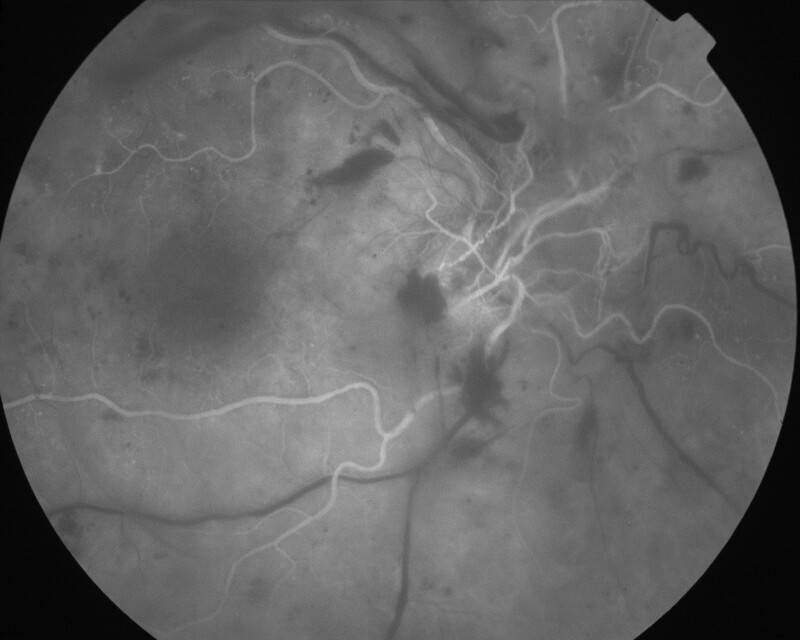

RETINOPATHIE DIABETIQUE PROLIFERANTE